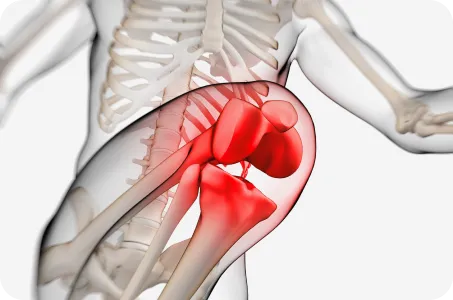

고관절 , 대퇴골, 경골, 거골, 중족골 중 어느 부위의 문제인지 정확히 파악하는 것이 중요합니다.

특히 거골이 안쪽으로 과도하게 틀어진 경우 6세 이후부터 서서히 그 굳어지기 때문에 6세이후에도 안짱걸음이 지속된다면 반드시 검사가 필요합니다.

대퇴골 내회전

허벅지 뼈가 안쪽으로 틀어진 경우